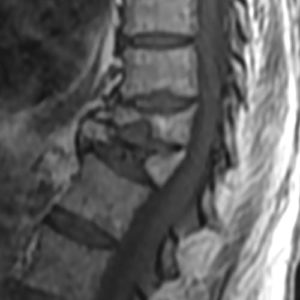

Dans la plupart des cas, le minimum est de 6 semaines. Fracture vertebrale en galette. Lors de la reprise du travail après une fracture vertébrale, la colonne vertébrale peut être stabilisée au début par un corset ou des bandes Kinesiotapes. Fracture vertebrale irm. En cas de travail physique lourd, l’incapacité de travail peut aller jusqu’à 6 mois (Fracture vertebrale lombaire). de la thérapie.

La durée du congé de maladie en cas de fracture vertébrale dépend de la gravité de la fracture (fracture vertébrale stable/instable) et de l’effort physique fourni au travail. Les patients qui ne travaillent qu’assis à leur bureau (activité sédentaire) peuvent reprendre plus tôt leur activité professionnelle quotidienne.